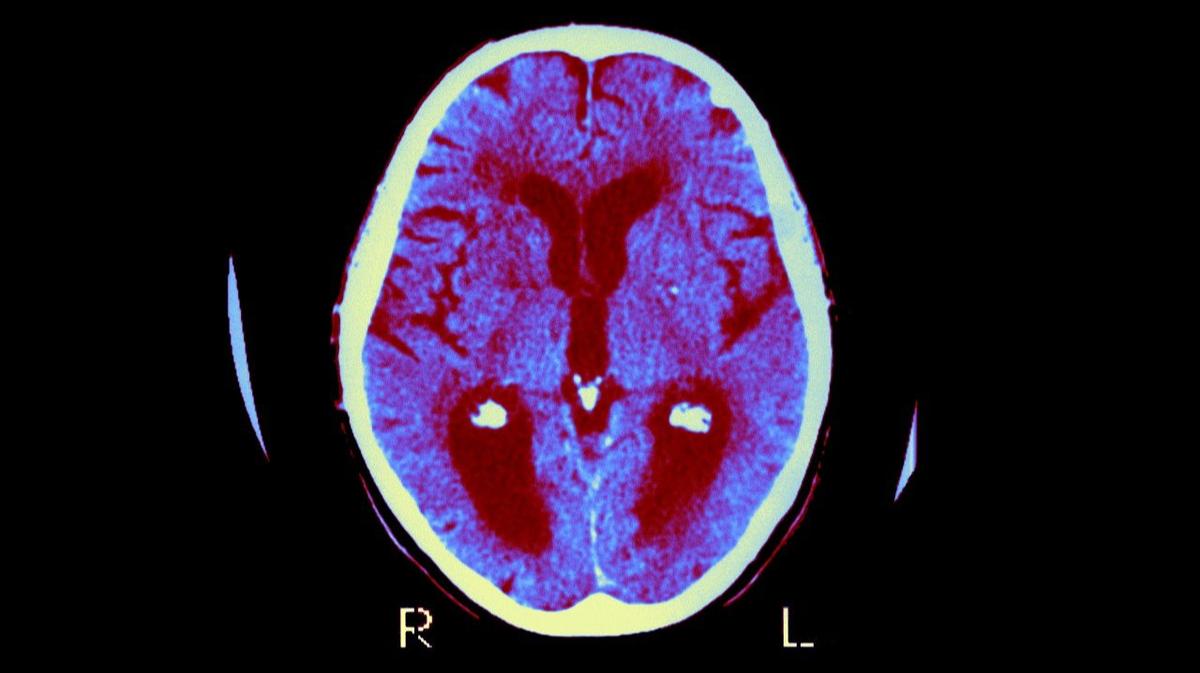

При болезни Альцгеймера в первую очередь страдают клетки участка головного мозга под названием гиппокамп (это часть височной доли), и они также гибнут быстрее, чем при обычном старении. Гиппокамп очень важен в процессе переработки и усвоении информации, перевода ее из оперативной памяти в долгосрочную. И поскольку именно эти клетки повреждаются при болезни Альцгеймера,

на первом месте из симптомов этого заболевания — прогрессирующее снижение краткосрочной (оперативной) памяти.

Дальше еще один важный аспект: одна из господствующих теорий для всех нейродегенеративных заболеваний гласит, что среди механизмов их развития главенствующую роль играют белки с нарушенной конформацией, с нарушенной трехмерной структурой. Это так называемая теория протеинопатий, она подкреплена доклиническими данными и данными аутопсий, свидетельствующими, что при нейродегенеративных заболеваниях тот или иной белок, который отличается в зависимости от конкретной болезни, по разным причинам может менять свою трехмерную структуру, менять свою конформацию, что изменяет его физические свойства.

Такие белки с нарушенной конформацией могут агрегировать, то есть образовывать нерастворимые комки, агрегаты, которые растут в размерах, накапливаются либо внутри нейрона, либо внутри клеток глии, либо снаружи, во внеклеточном пространстве.

Такое накопление нерастворимых агрегатов, которые невозможно вывести из головного мозга, приводит в конечном счете к гибели нейронов

либо напрямую, либо опосредованно через, например, страдание функции клеток глии: эти клетки поддерживают функции нейронов. И в зависимости от конкретной нейродегенеративной болезни белок, который образует эти нерастворимые агрегаты, может быть разным.

Да, и к слову, это может быть не обязательно один белок, это может быть сразу несколько белков. При болезни Паркинсона — это альфа-синуклеин, при болезни Альцгеймера — это бета-амилоид, который накапливается во внеклеточном пространстве, то есть снаружи нейрона, и так называемый тау-белок, который накапливается внутри нейрона. И всё осложняется тем, что у этих белков есть ещё свои изомеры, подтипы, которые имеют определенное отличие по своим размерам и структуре. И, например, при болезни Альцгеймера этот тау-белок имеет тоже несколько своих подтипов: 3R и 4R. Таким образом, при болезни Альцгеймера в головном мозге накапливаются и 3R-белок, и 4R тау-белок в сочетании с бета-амилоидом.

Это практика, которая в России, к сожалению, игнорируется: когда человек с нейродегенеративным заболеванием погибает, специализированное иммунногистохимическое исследование образцов головного мозга на эти белки в России не проводится рутинно. Если у человека есть болезнь Альцгеймера, мы сможем поставить этот диагноз, если при иммунногистохимическом исследовании мы выявляем, что да, есть бета-амилоид в межклеточном пространстве и 3R и 4R тау-белок внутри нейронов, а также доминирует поражение именно гиппокампов в височных долях. Стоит, правда, отметить, что по мере прогрессирования заболевания патологические бета-амилоид и тау-белок, безусловно, распространяются по всему головному мозгу. Есть, к слову, и атипичные формы болезни Альцгеймера, которые могут начинаться с атрофии не височных долей, не гиппокампа, а, например, лобных или затылочных долей. И тогда на первом месте будут симптомы не со стороны оперативной памяти, а, например, если это затылочная доля поражена, то будет страдать восприятие текста, и человек будет жаловаться на то, что он видит текст, но не может его прочитать. Но пациенты не могут прочитать не потому, что у них плохое зрение, а потому, что кора не может обработать поступающий зрительный сигнал должным образом.